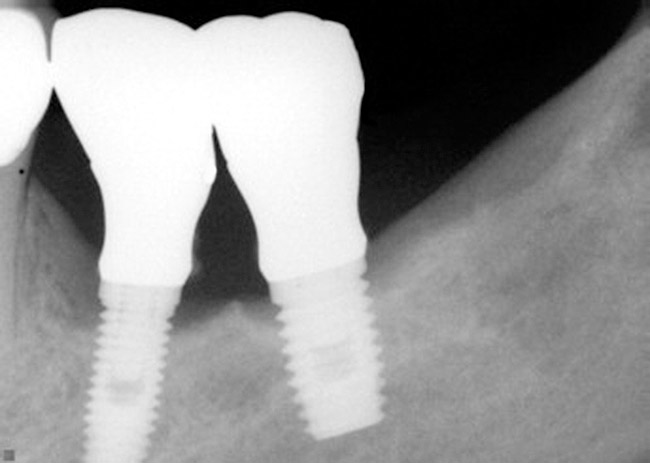

Radiographically, in peri-implantitis, vertical destruction of the crestal bone is present around the implant—which assumes the shape of a saucer—while the bottom part of the implant remains osseointegrated. In some instances, wedge-shaped defects develop along the implant (Figure 1). In addition, there is a peri-implant pocket and bleeding after gentle probing with a blunt instrument, and there may be suppuration from the pocket (Figure 2 and Figure 3). Tissues may or may not be swollen; however, hyperplasia is frequently seen if implants are located in an area with non-keratinized mucosa or if the suprastructure is an overdenture. Pain is not present.9 Both a mean loss of peri-implant bone height amounting to 1 mm to 1.5 mm in the first postsurgical year and vertical bone loss of less than 0.2 mm annually following the implant’s first year of service have been proposed as major criteria for success.18-20 It should be noted that peri-implant bone loss also occurs in cases of overload and faulty occlusion and may be be related to the type of implant used. The implants with the longest smooth surfaces demonstrated the highest amounts of bone resorption 12 months after abutment connection.21 Mobility of an implant suggests complete bone loss and, therefore, complete failure. To prevent this, peri-implant disease should be recognized earlier, to allow intervention before a substantial portion of the supporting bone is lost. However, mobility in early periods of osseointegration is not a very reliable clinical indicator of peri-implantitis. Therefore, electronic measuring devices should be used.

Figure 3